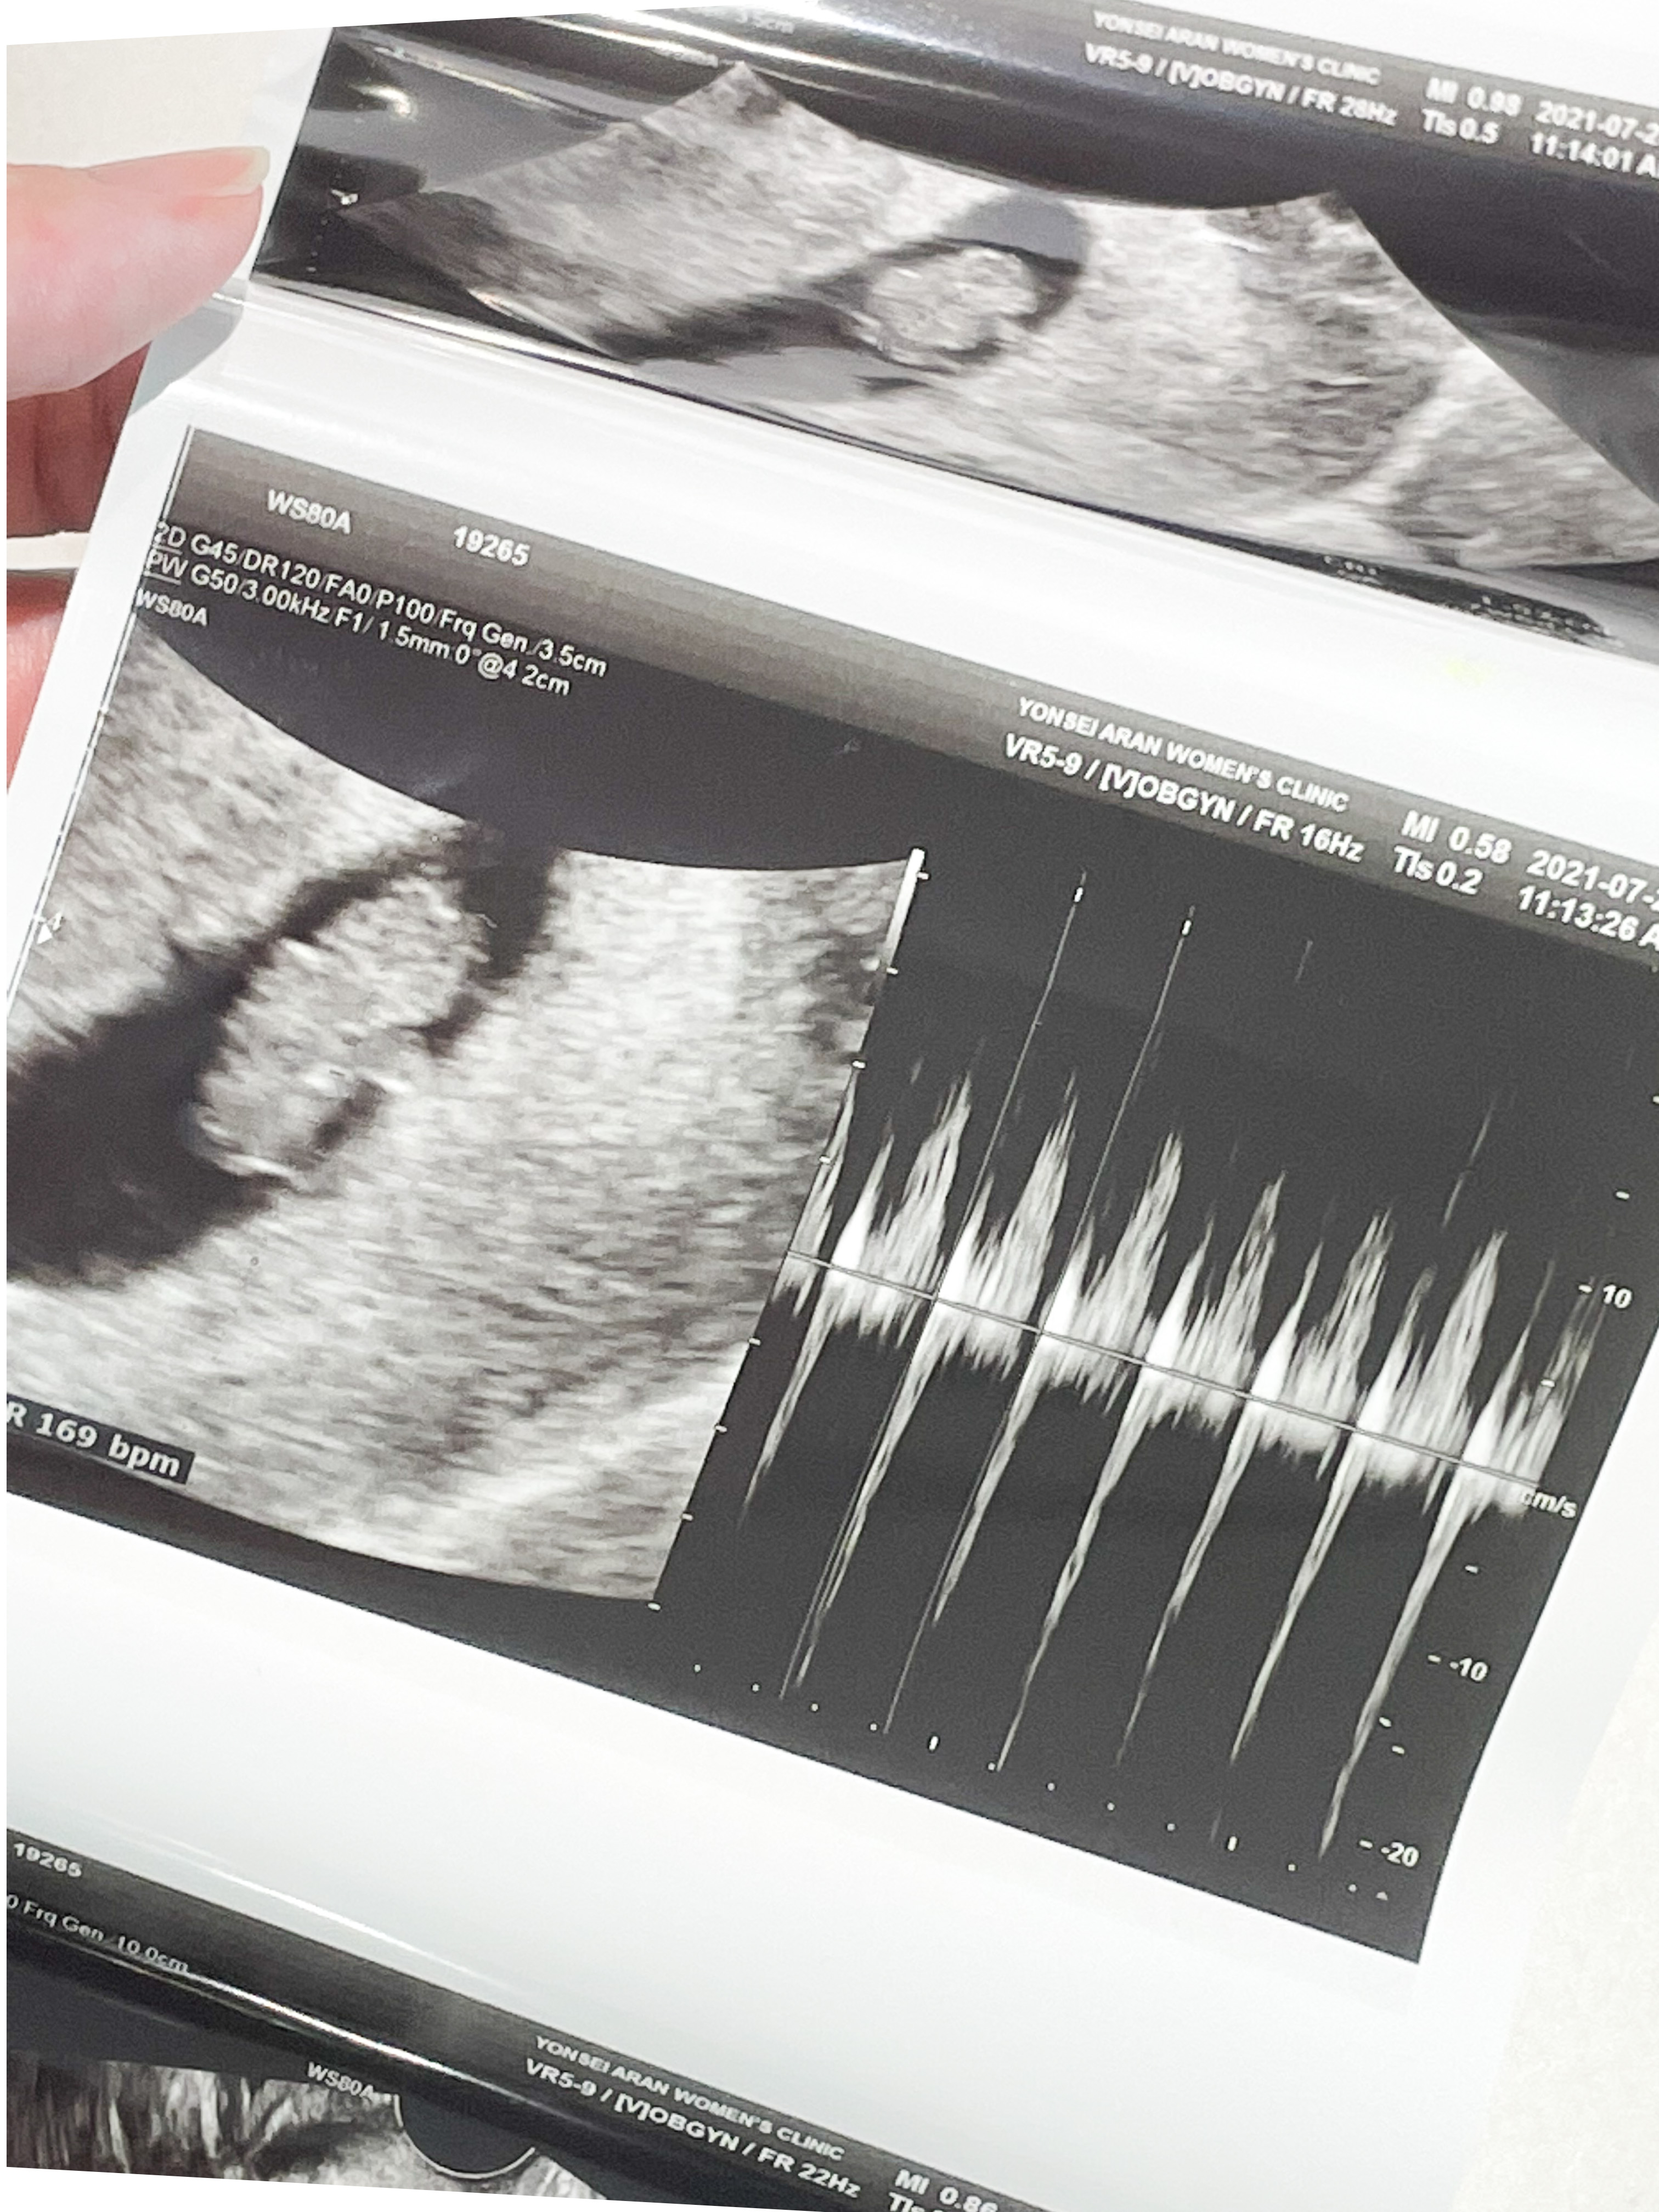

8주 1일

입덧약 처방 받으러 간 김에 초음파도 한 번 봤다.

막대기 같이 생겼던 아기가 어느덧 통통해졌고 팔다리까지 있었다.

쌤이 젤리곰이라고 너무 귀엽다고 하셨는데,

내 눈에는 물개 같았다.

심장도 잘 뛰고 있었다.